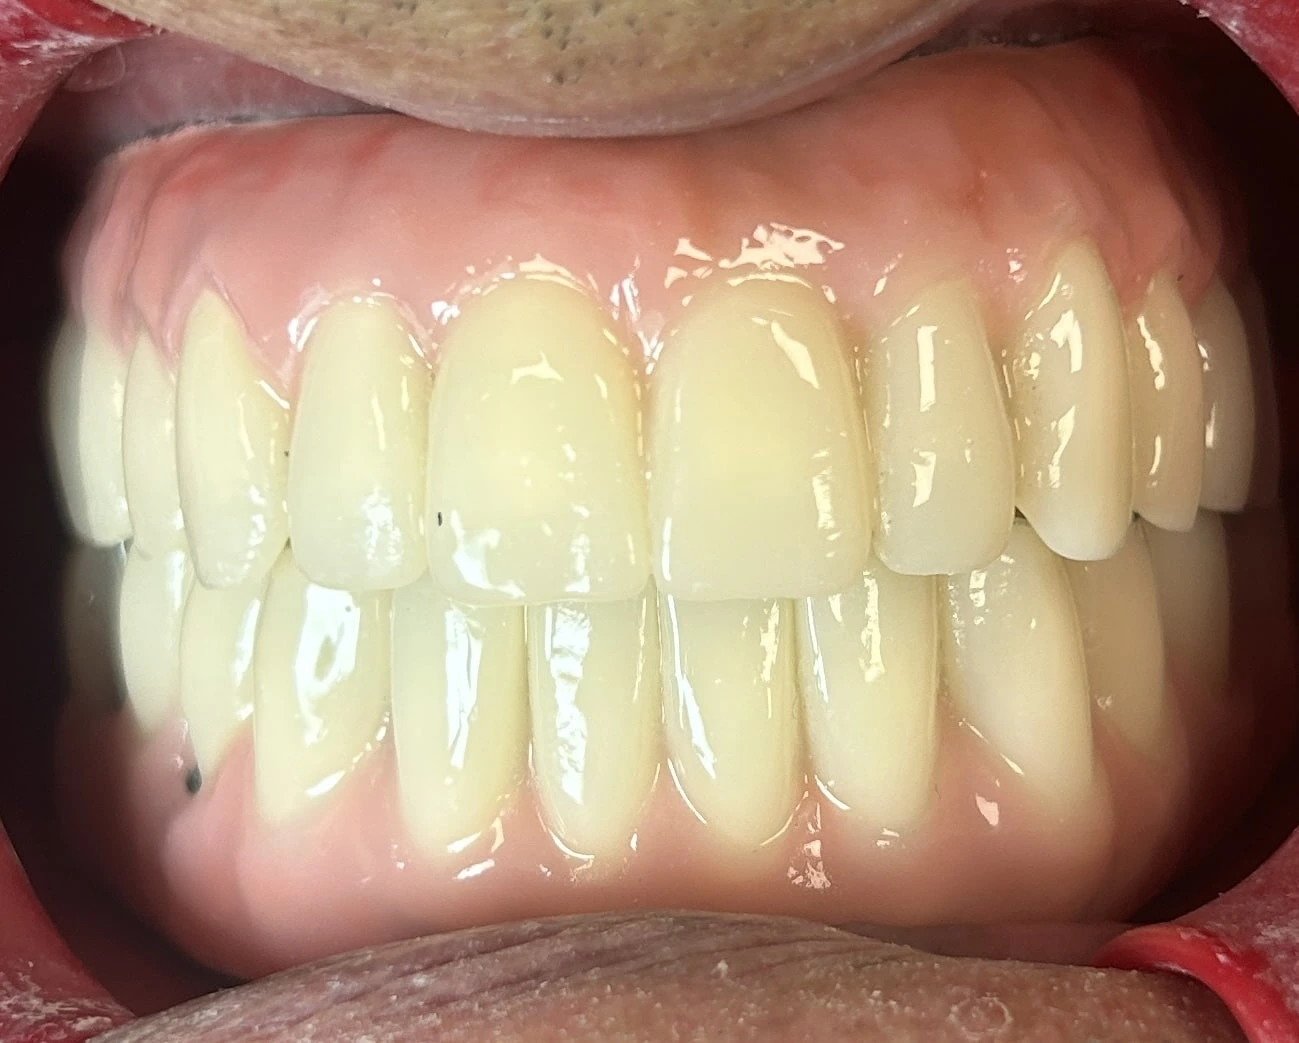

• Applicazione della corona o della protesi definitiva, progettata per armonizzarsi con estetica e funzionalità.

La Toronto Bridge è una protesi fissa avvitata agli impianti, costituita da una struttura in metallo o zirconia che sostiene denti in ceramica o composito.

Protesi tipo Toronto Bridge su impianti

• Caratteristiche principali

• Stabilità assoluta.

• Ottimo risultato estetico.

• Possibilità di rimozione in studio per la manutenzione, senza danneggiare l’impianto o la protesi.

• Indicazioni: pazienti completamente edentuli o con denti residui non recuperabili che desiderano una soluzione definitiva e duratura.